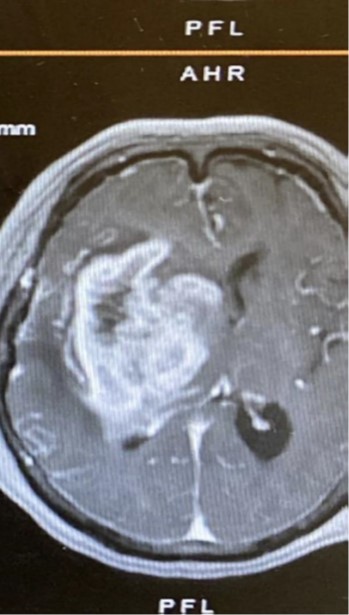

顱內壓機制有兩項已提高,患者頭痛痛醒和嘔吐,嘔吐後才舒緩,因為腦內血液量下降,機制也重新平衡。所以晨起頭痛是包括頭痛痛醒、嘔吐和嘔吐後舒缓三點。有此症狀要馬上找神經外科醫生安排檢查,醫生多數建議做磁力共振掃描。